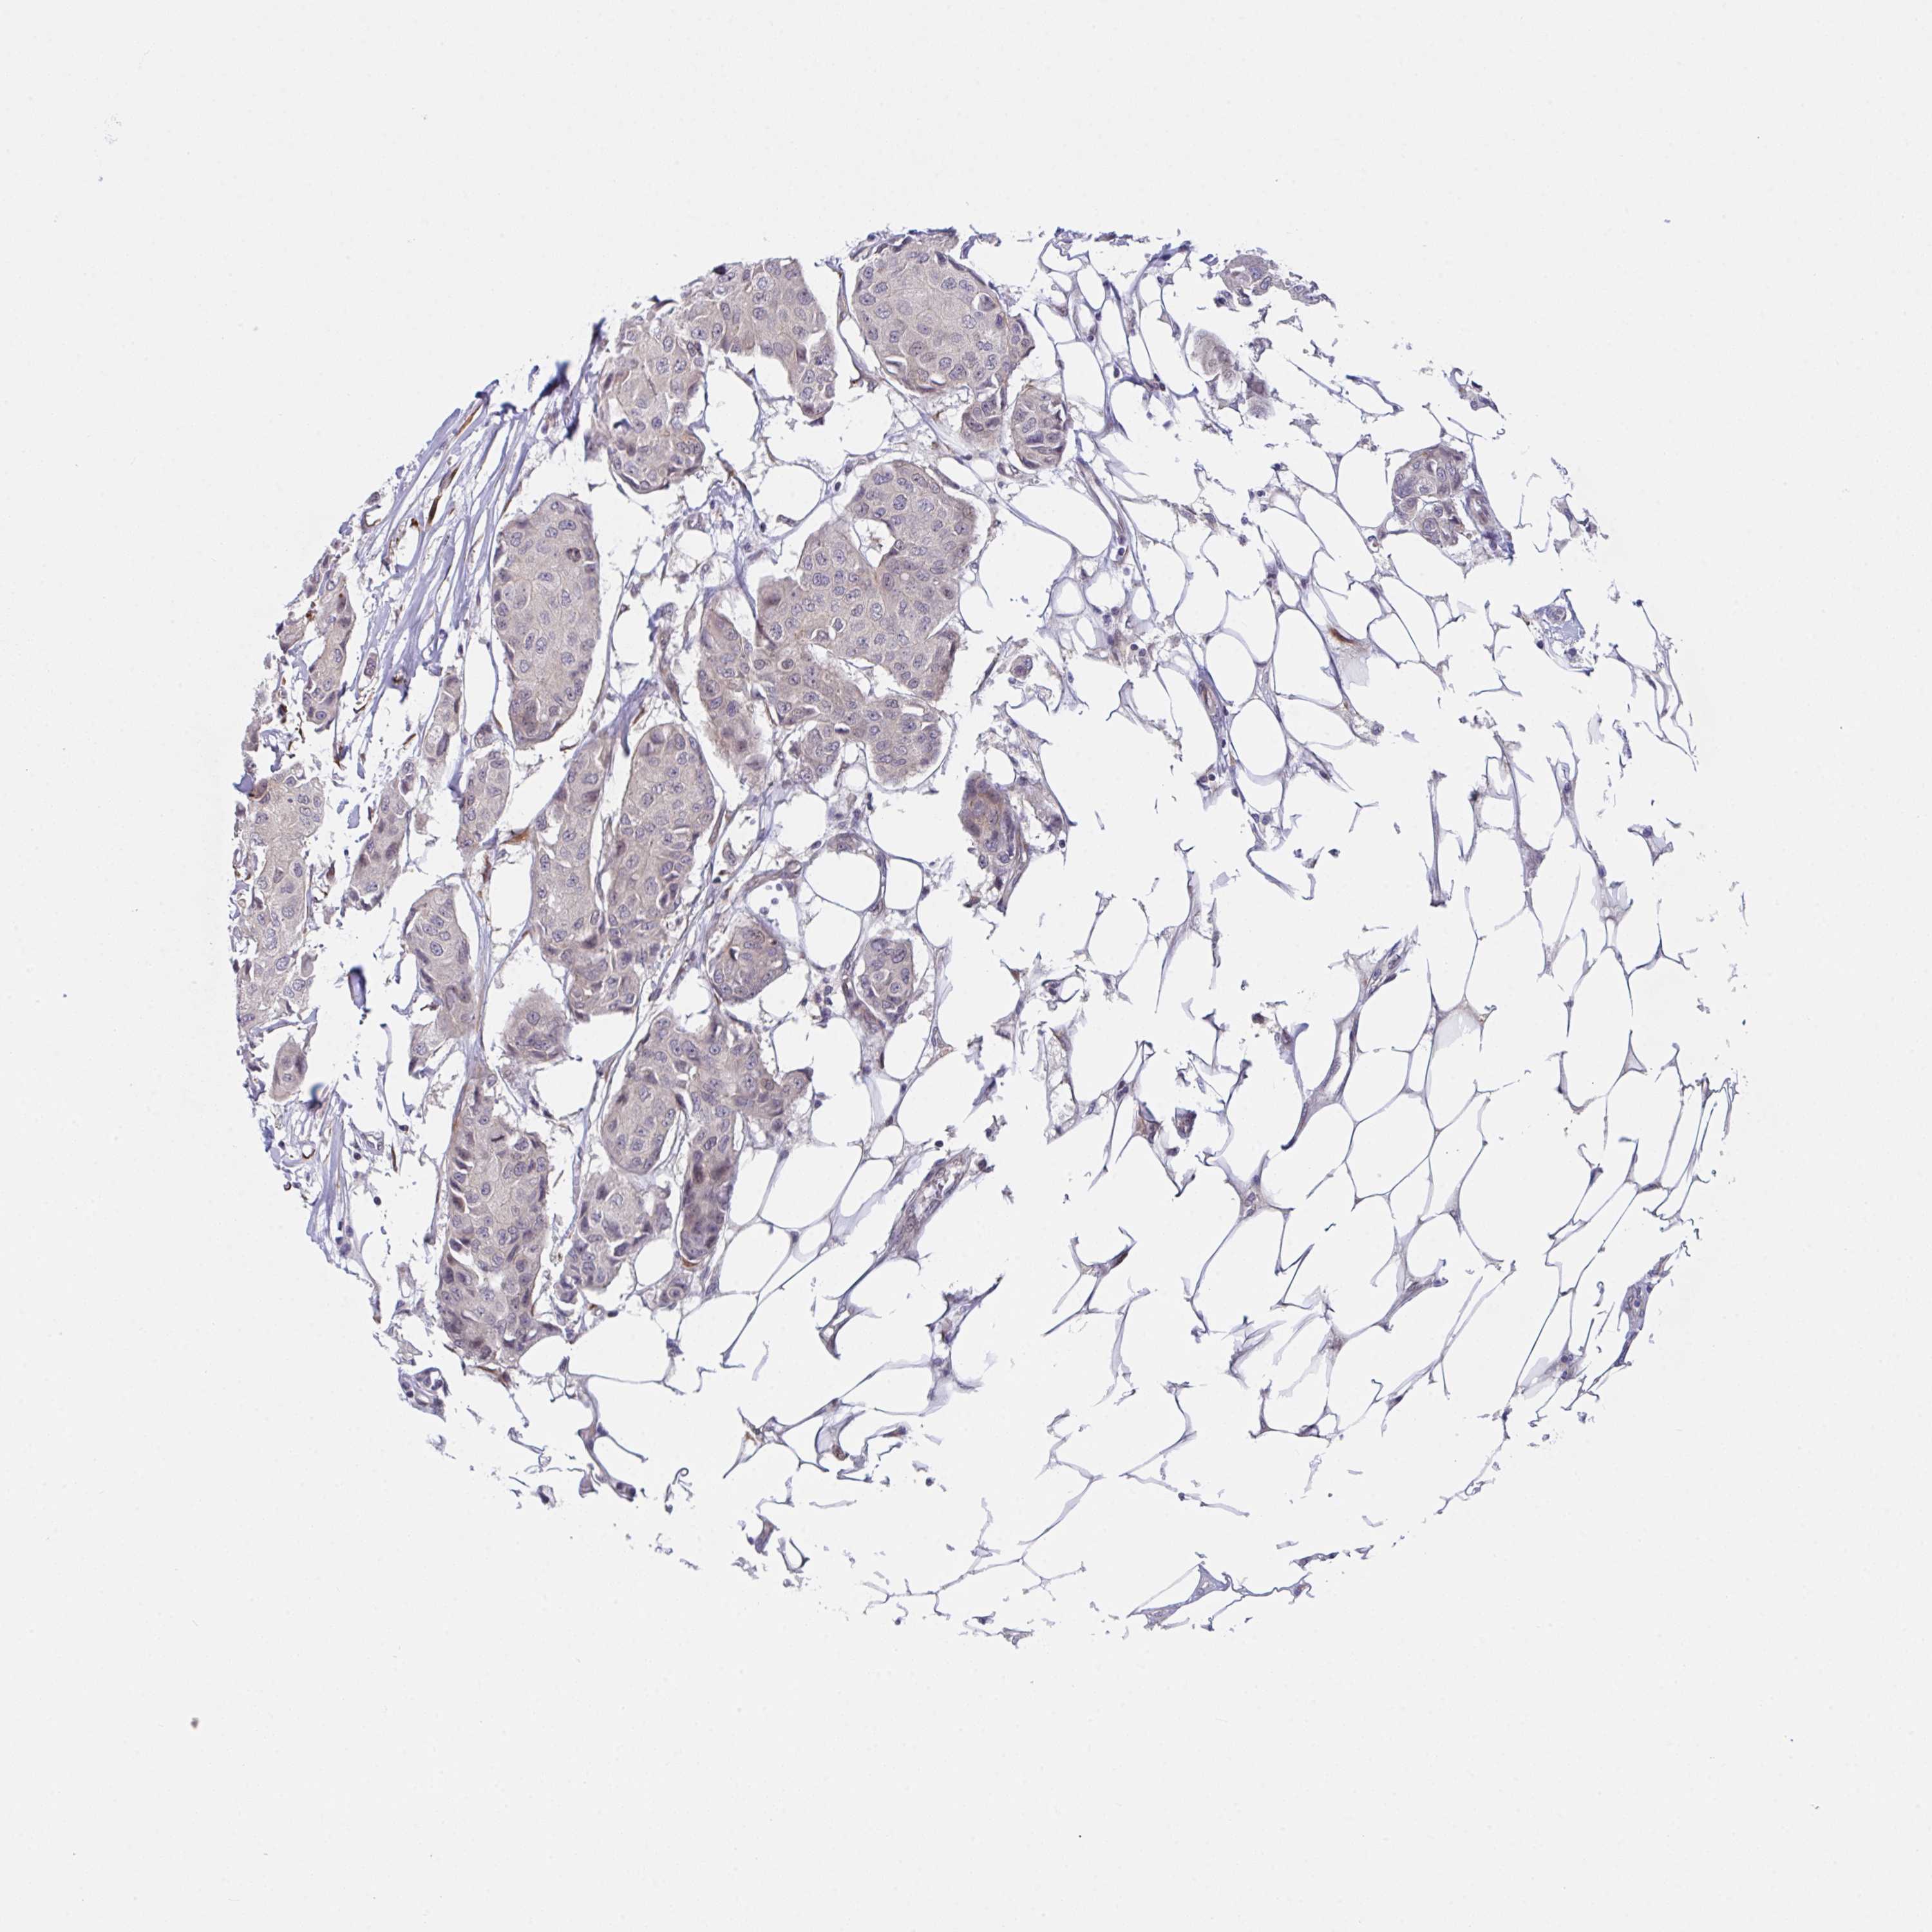

Breast cancer

Human cancer